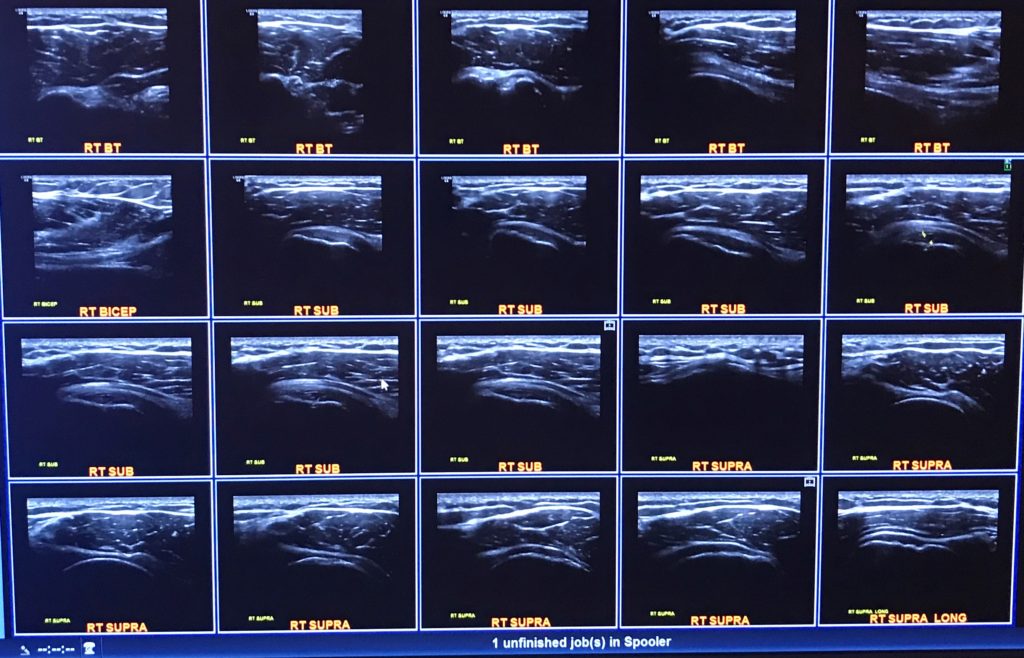

As Dok can attest, that right there is a completely torn supraspinatus with a burst bursa sac & dipped deltoid. In normal English, it’s a fully torn rotator cuff that will require surgery. The tendon has been ripped from the bone.